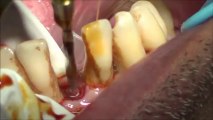

A single dental implant placement without bone graft-india

Our vision is to give a good quality implant treatment to our patient.We have a team of experienced doctors under DR MURUGAVEL with the back up advanced technology.visit us at http://bestlaserdentalclinic.com (or) http://www.drmurugavel.in/